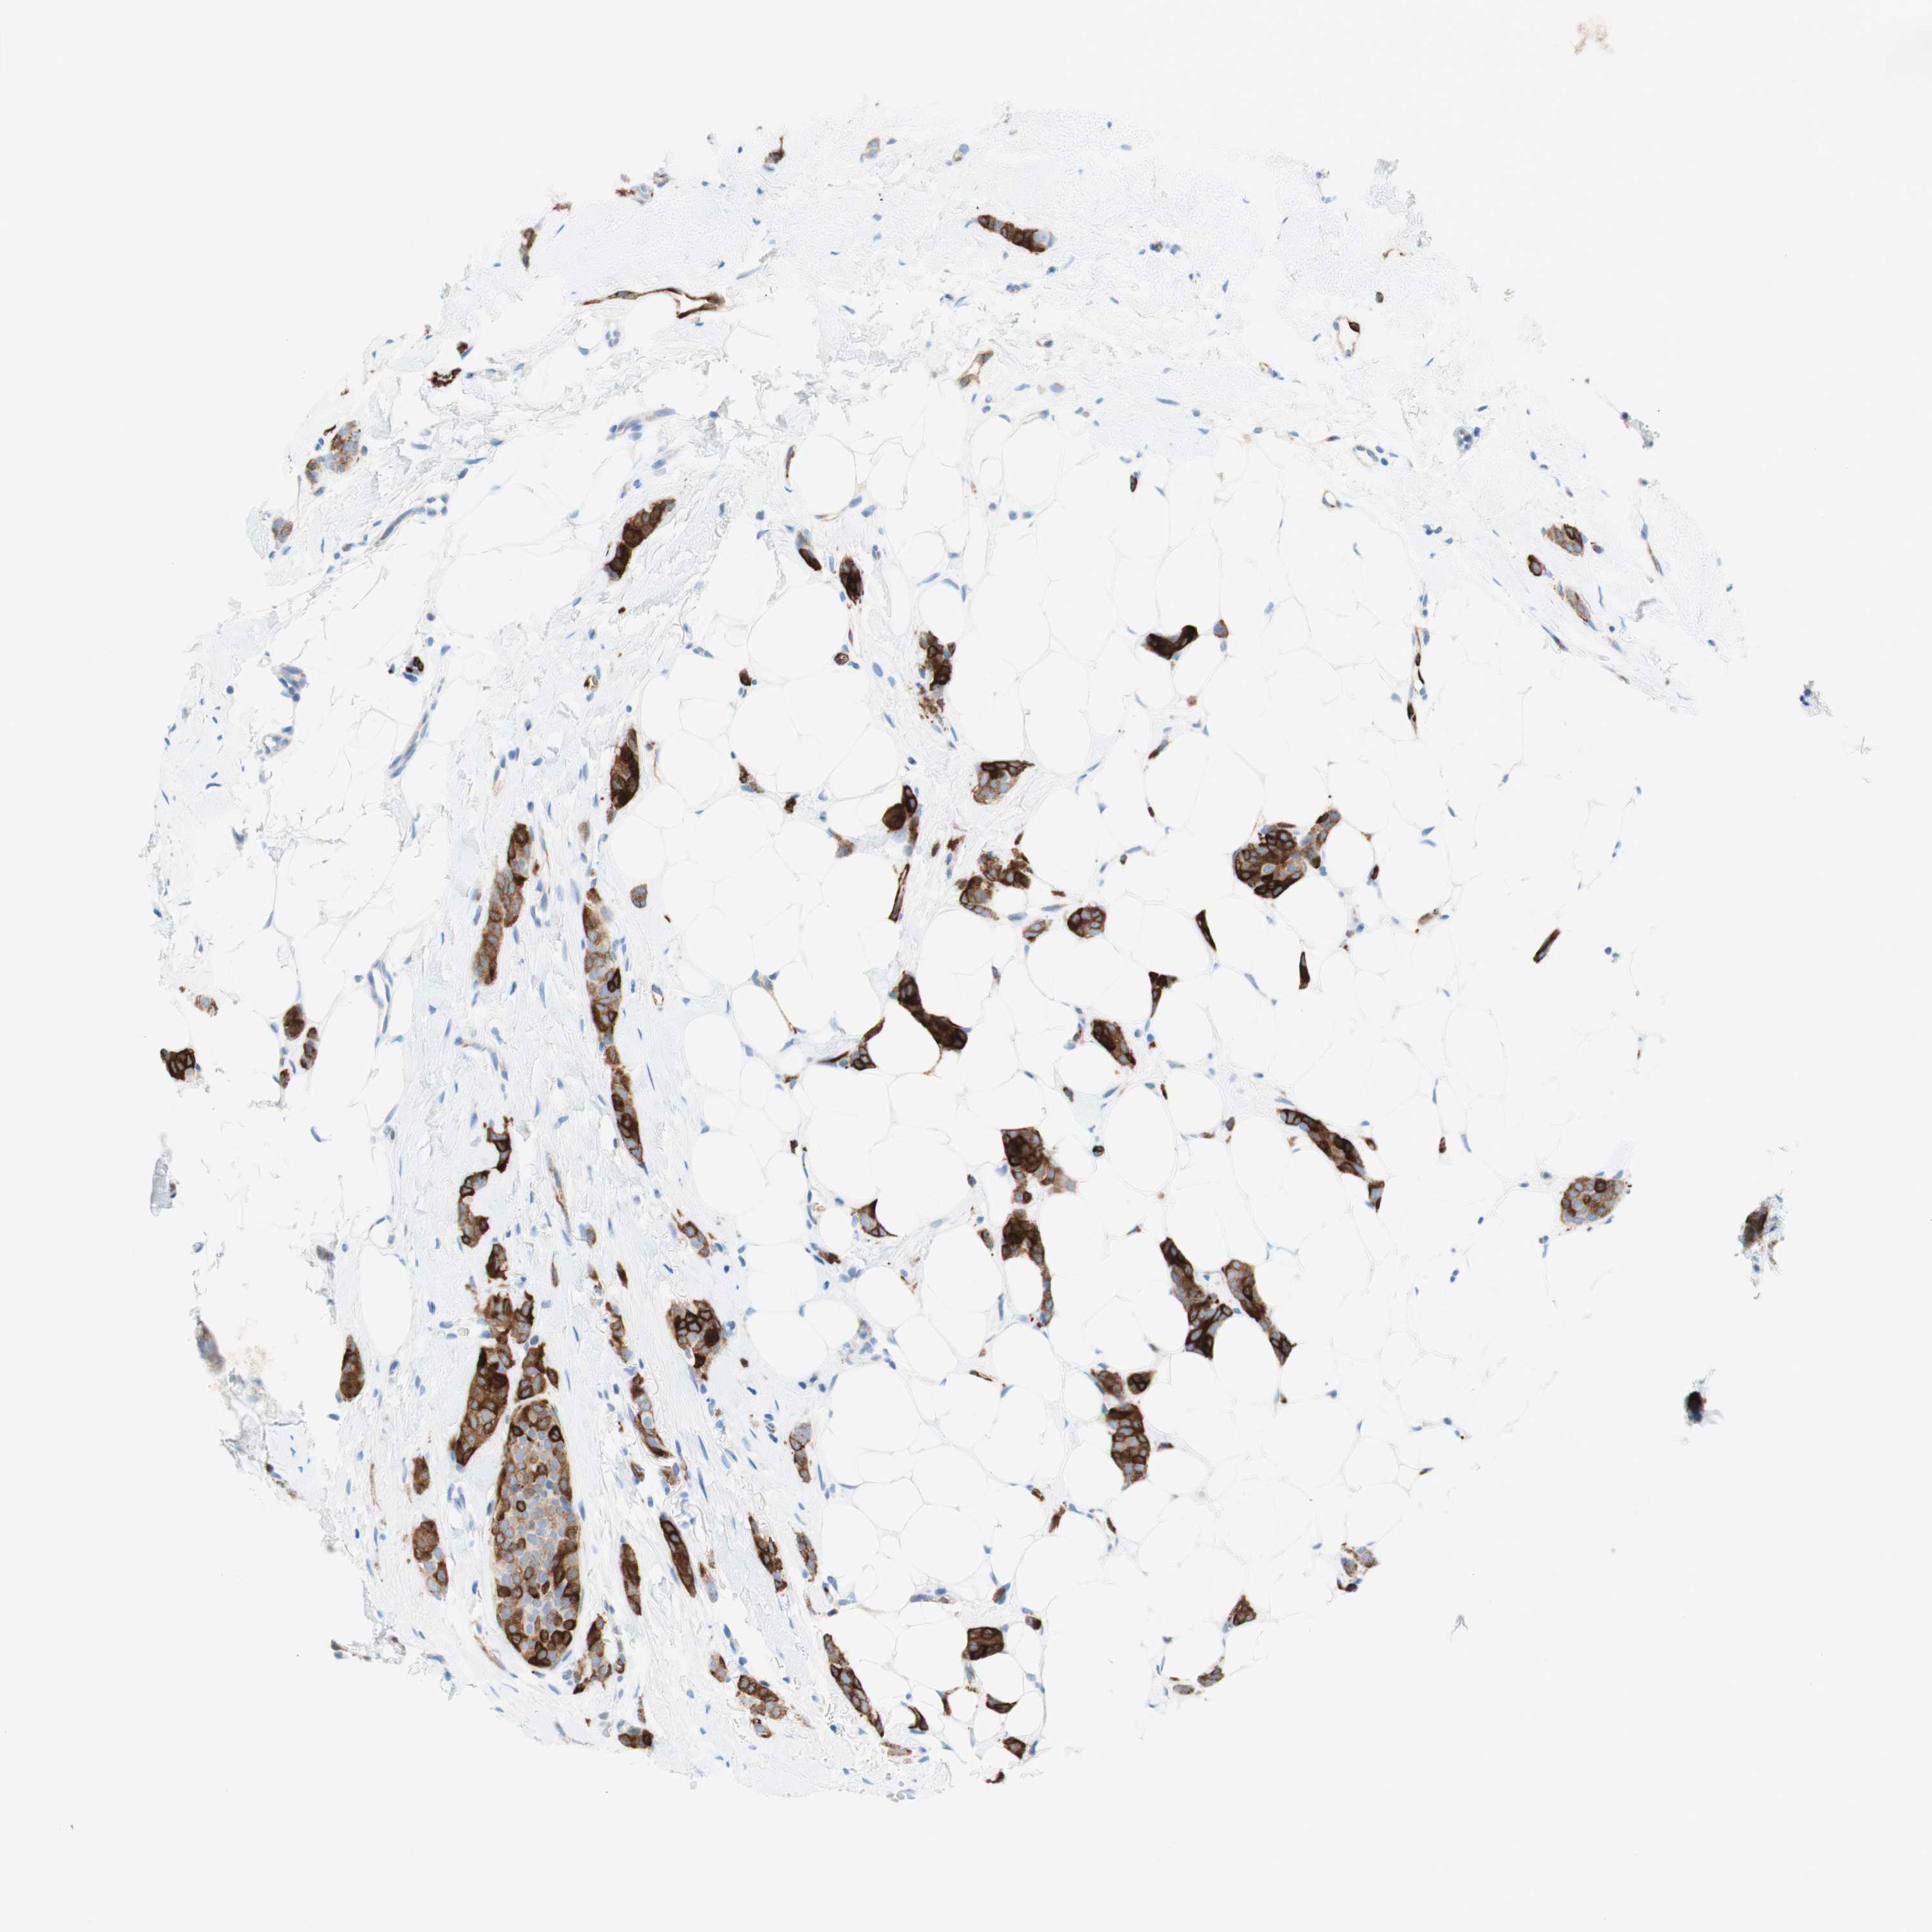

CANCER BREAST CANCER Show tissue menu

BRCA TCGA BRCA VALIDATION PROTEIN EXPRESSION